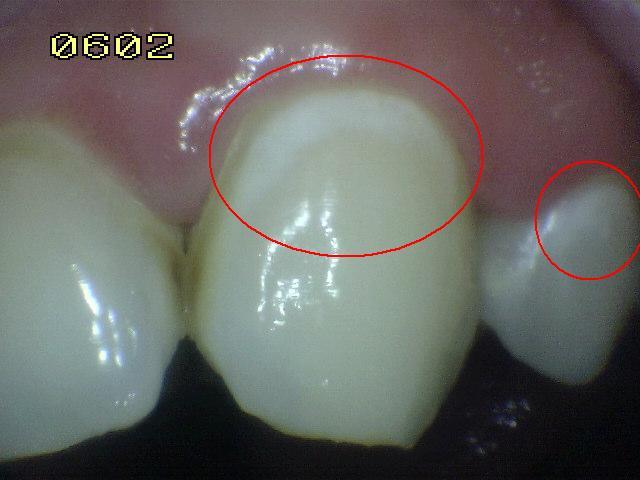

2. CAVIDAD EXTENSA, DENTINA CLARAMENTE EXPUESTA

1. ACTIVIDAD

2. HALLAZGO CLINICO

1. Cavida extensa

2. DIAGNÓSTICO

1. lesión cariosa cavitacional con exposición de dentina

1. ICDAS 6

2. TRATAMIENTO

1. operatoria

1. promoción y precvención